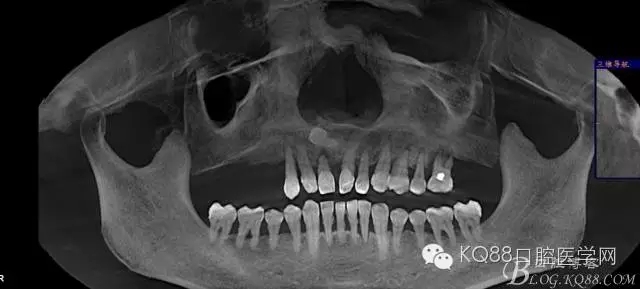

輔助檢查:ct示骨密度良好,11 12區(qū)域骨下有一水平向埋伏牙,15 16區(qū)域骨高度2.5-3mm,骨寬度6-9mm。